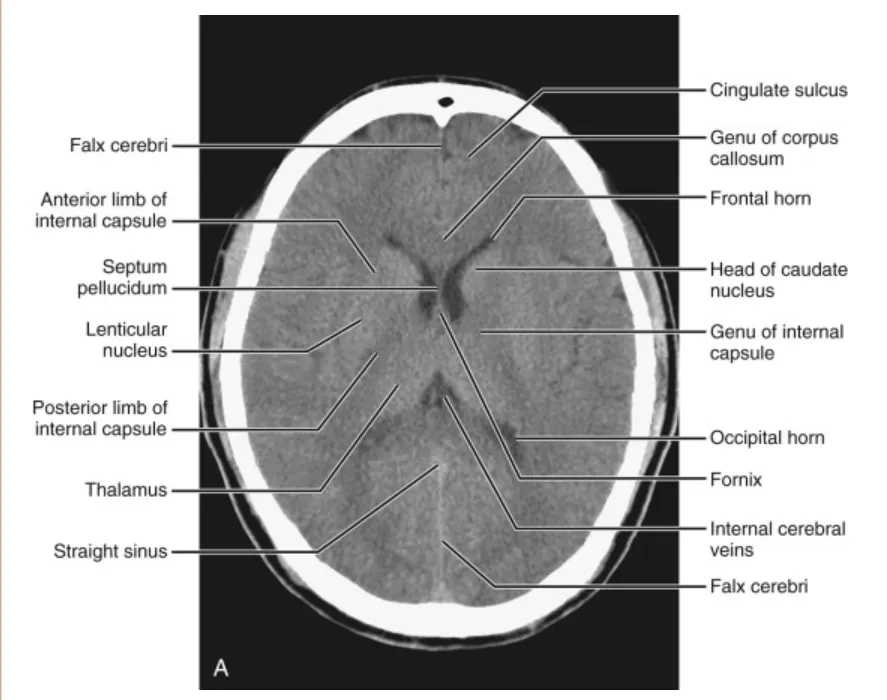

(해설) Brain CT의 각 Level 별로 보이는 구조물입니다.

(2) Low ventricular level

전두엽(frontal lobes)의 가장 상부가 보입니다. 전각(frontal horns)의 상부는 측면으로 미상핵두부(head of the caudate nuclei)에 의해 윤곽이 그려집니다. 전방으로 전각은 뇌량팽대(genu of the corpus callosum)의 함입에 의해 형성됩니다. 뇌량(corpus callosum)은 대상회구(cingulate sulcus)에 의해 대상회(cingulate gyrus)와 분리되어 보입니다. 후방으로 후각(occipital horns)은 뇌량팽(splenium of the corpus callosum)에 의해 함입됩니다. 측뇌실(lateral ventricle) 내에서 맥락얼기(choroid plexus)가 MRI에서 확인될 수 있습니다. 뇌량팽 뒤쪽으로 직정맥동(straight sinus)이 일반 MRI에서 신호 소실(signal void)로 나타납니다.